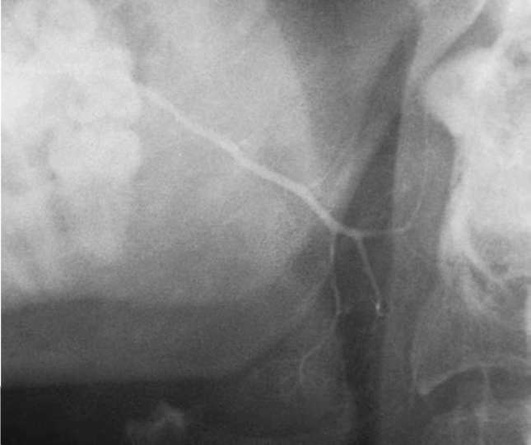

Диагностика. В распознавании слюннокаменной болезни имеет значение не только обнаружение камня, но и выявление причины камнеобразования. Анамнестический признак в виде слюнной колики в 99% случаев позволяет предположить наличие конкремента. На обзорных рентгенограммах рентгеноконтрастные камни хорошо визуализируются (рис. 6.11-6.13), на сиалограммах они видны в виде очага дефекта наполнения контрастного вещества. На эхосиалограммах камни видны по типу «звуковой дорожки». Особенно часто (более чем в 99%) камни выявляются на компьютерных томограммах.

image

Рис. 6.11. Рентгенограмма черепа в прямой проекции. В области левой околоушной железы определяется конкремент